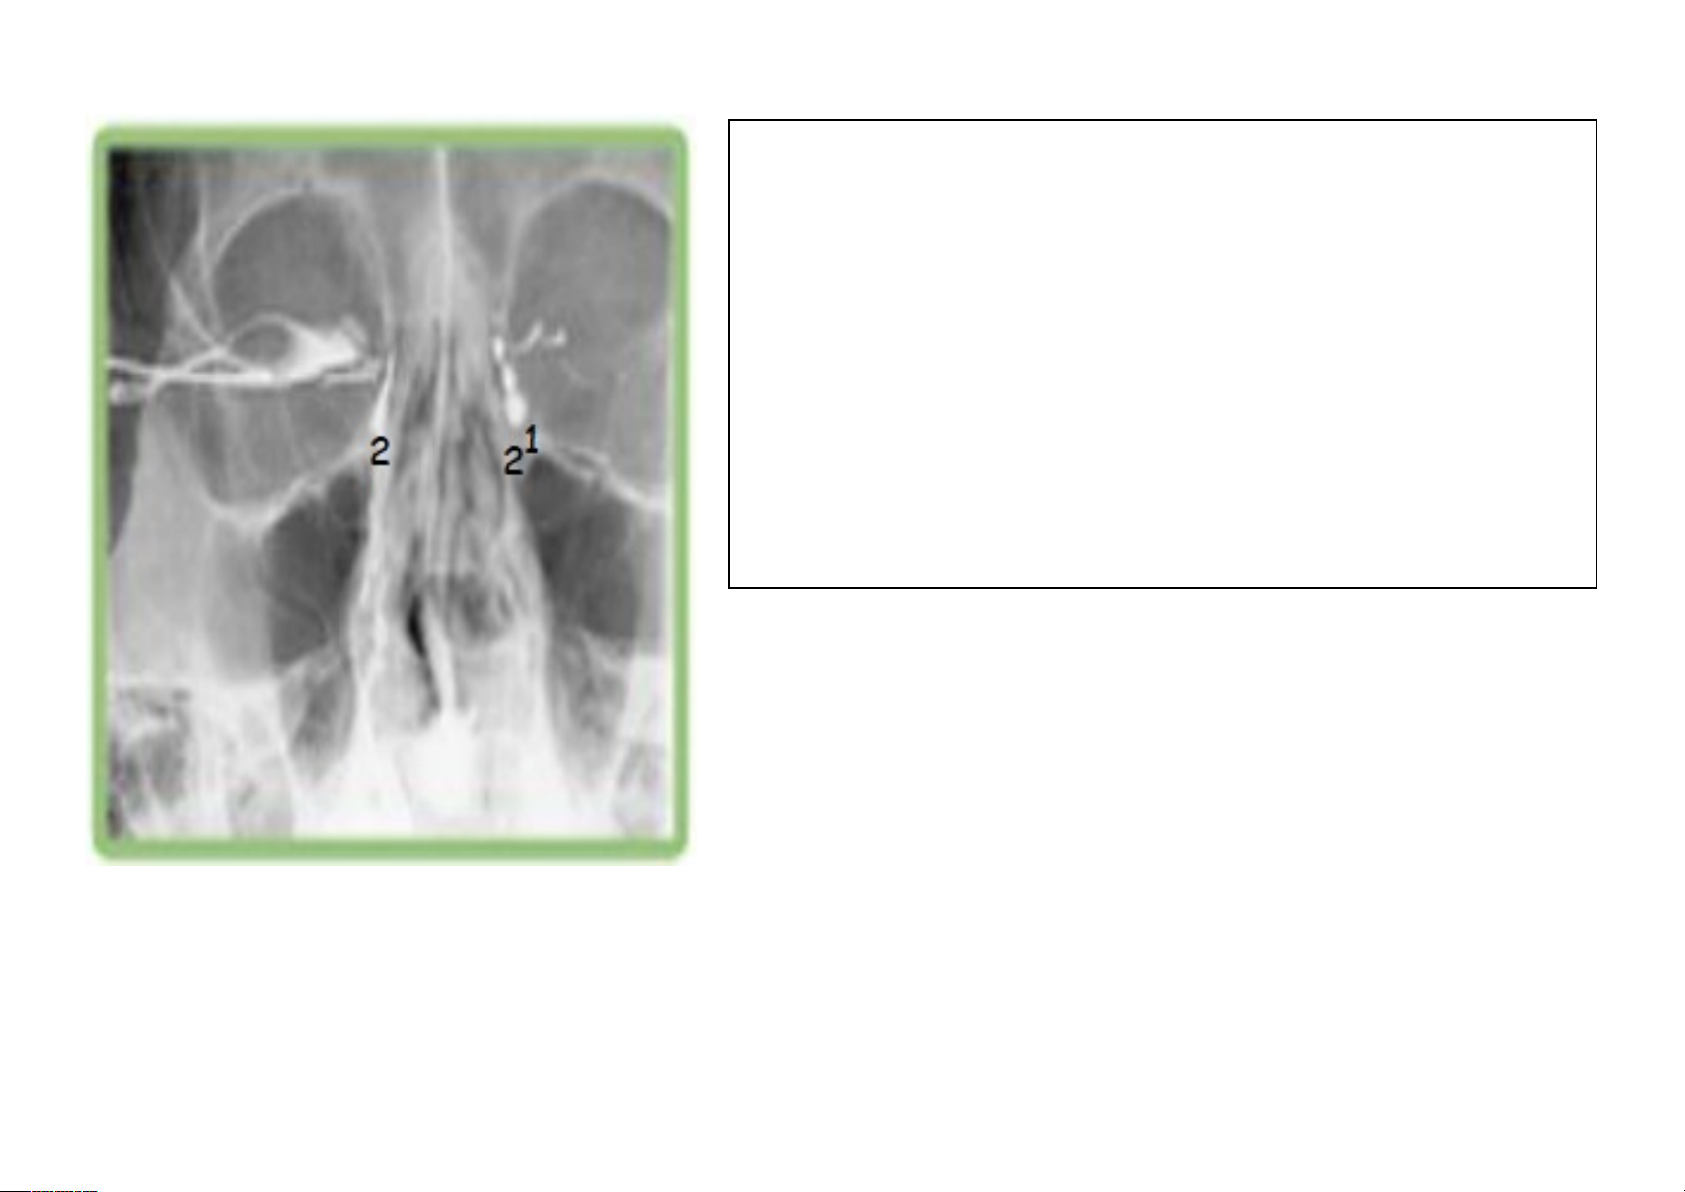

IMAGEM 3

NOME DO EXAME: Dacriocistografia

MEIO DE CONTRASTE: Iodado + soro fisiológico, via ducto lacrimal

POSICIONAMENTO: AP localizada das órbitas

AP devido os ductos lacrimais serem visualizados magnificados

PATOLOGIA: Estenose nos ductos lacrimais, devido o estreitamento do lado esquerdo e devido a falha de preenchimento de contraste do lado direito.

ANATOMIA RADIOLÓGICA:

- Ductos lacrimais

INÍCIO E TÉRMINO DO EXAME: Ductos lacrimais